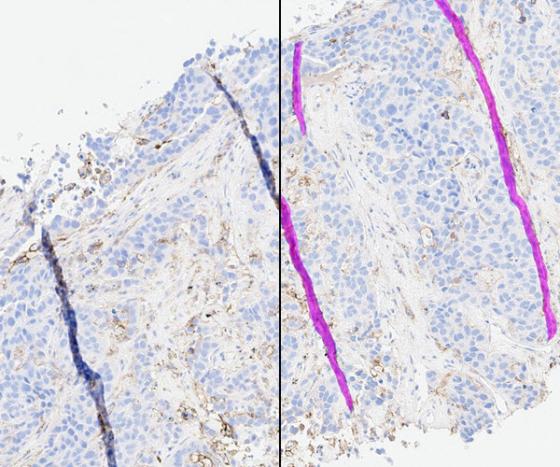

After selecting an image, view the H&E or IHC slide in the viewer and the SlideQC BF results. Results include overlays and quantitative results. The overlay highlights artifacts in magenta and acceptable tissue areas in cyan.